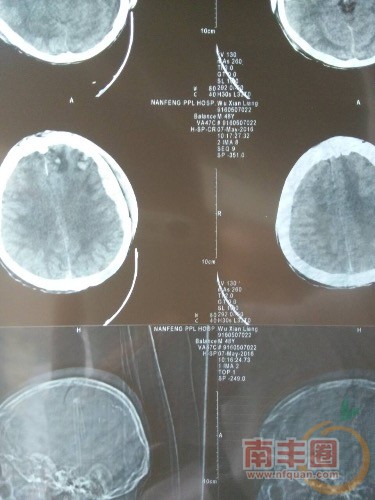

事情是这样的,下面在病床上躺着的是我一位朋友的父亲,家住江西省抚州市南丰县洽湾镇浆坑村店前组,起因是因为去火车站买票前往南昌照顾因肾结石正在动手术的二弟,在路上因为公路维修没有安放警示牌出了车祸,导致脑部严重受伤,目前一直处于昏迷状态,随时都有生命危险。我朋友三叔又在一年前失踪至今杳无音讯,本来已经拮据的家庭,早已折腾的花完了,医生说后期治疗还需要20到30万,对于他们来说简直就是天文数字,我朋友也不怎么会用微信,所以这些情况我帮他代发的,下面是他父亲的一些基本情况还有他家的个人资料,以证明事实属实!               当然现在骗子也很多,所以大家在献爱心的时候请一定要联系本人,或者直接去南丰县人民医院住院部一楼ICU病房,。          吴强联系电话13879499352。 建行卡号 6259063667657202 中国银行户主 吴强。 6217002090002006958 建设银行 户主吴强。   个人资料真实可供查询,望各位路过看到这篇文章的朋友能帮忙扩散让更多的人知道,也让更多的人能帮帮这个家庭,。最后重申一遍,捐款的朋友不论多少一定要先和他本人联系,和他本人联系,和他本人联系, 最后在此先谢过各位朋友了,同时也希望朋友的父亲能尽快好起来!

原本清晰的图片发出来却有点模糊了,不过没事,质疑的朋友可以拨打事主儿子的电话,13879499352

也可以前往南丰县人民医院住院部一楼ICU病房查证,病人吴先亮